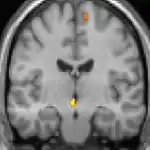

La tomographie par émission de positons (TEP) montre les zones du cerveau étant activées durant la douleur

Les images par tomographie à émission de positron indiquent les régions du cerveau qui sont activées lors de la douleur, par rapport aux périodes sans douleur. Elles montrent les régions du cerveau qui sont toujours actives durant la douleur en jaune/orange (appelé "matrice-douleur"). La zone au centre (dans les trois vues) est spécifiquement activée uniquement pendant la crise. Les photos sur la ligne du bas (effectuées par VBM) montrent les différences structurelles entre les patients souffrant d'AVF et des personnes saines : seulement une partie de l'hypothalamus est différente[50],[51].